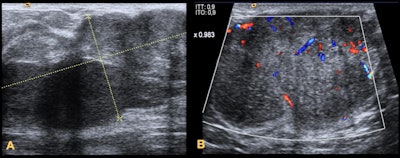

- In children, when necessary, the initially recommended imaging technique is breast ultrasound.

- Mammograms should be performed only in patients with lesions not completely clarified by ultrasound as a complementary technique depending on initial findings and the degree of suspicion.